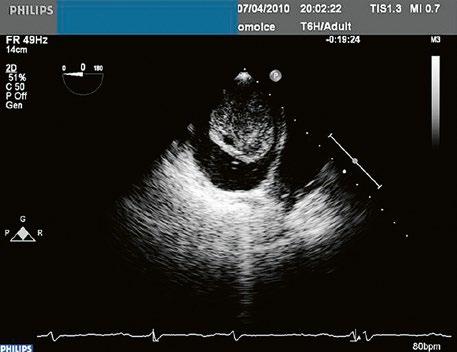

45.14 Univentrikulární srdce, Fontanovská cirkulace, TCPC (totální kavopulmonální spojení, total cavo-pulmonary connection) ................................................................ 1094

Léčba a sledování .........................................................................